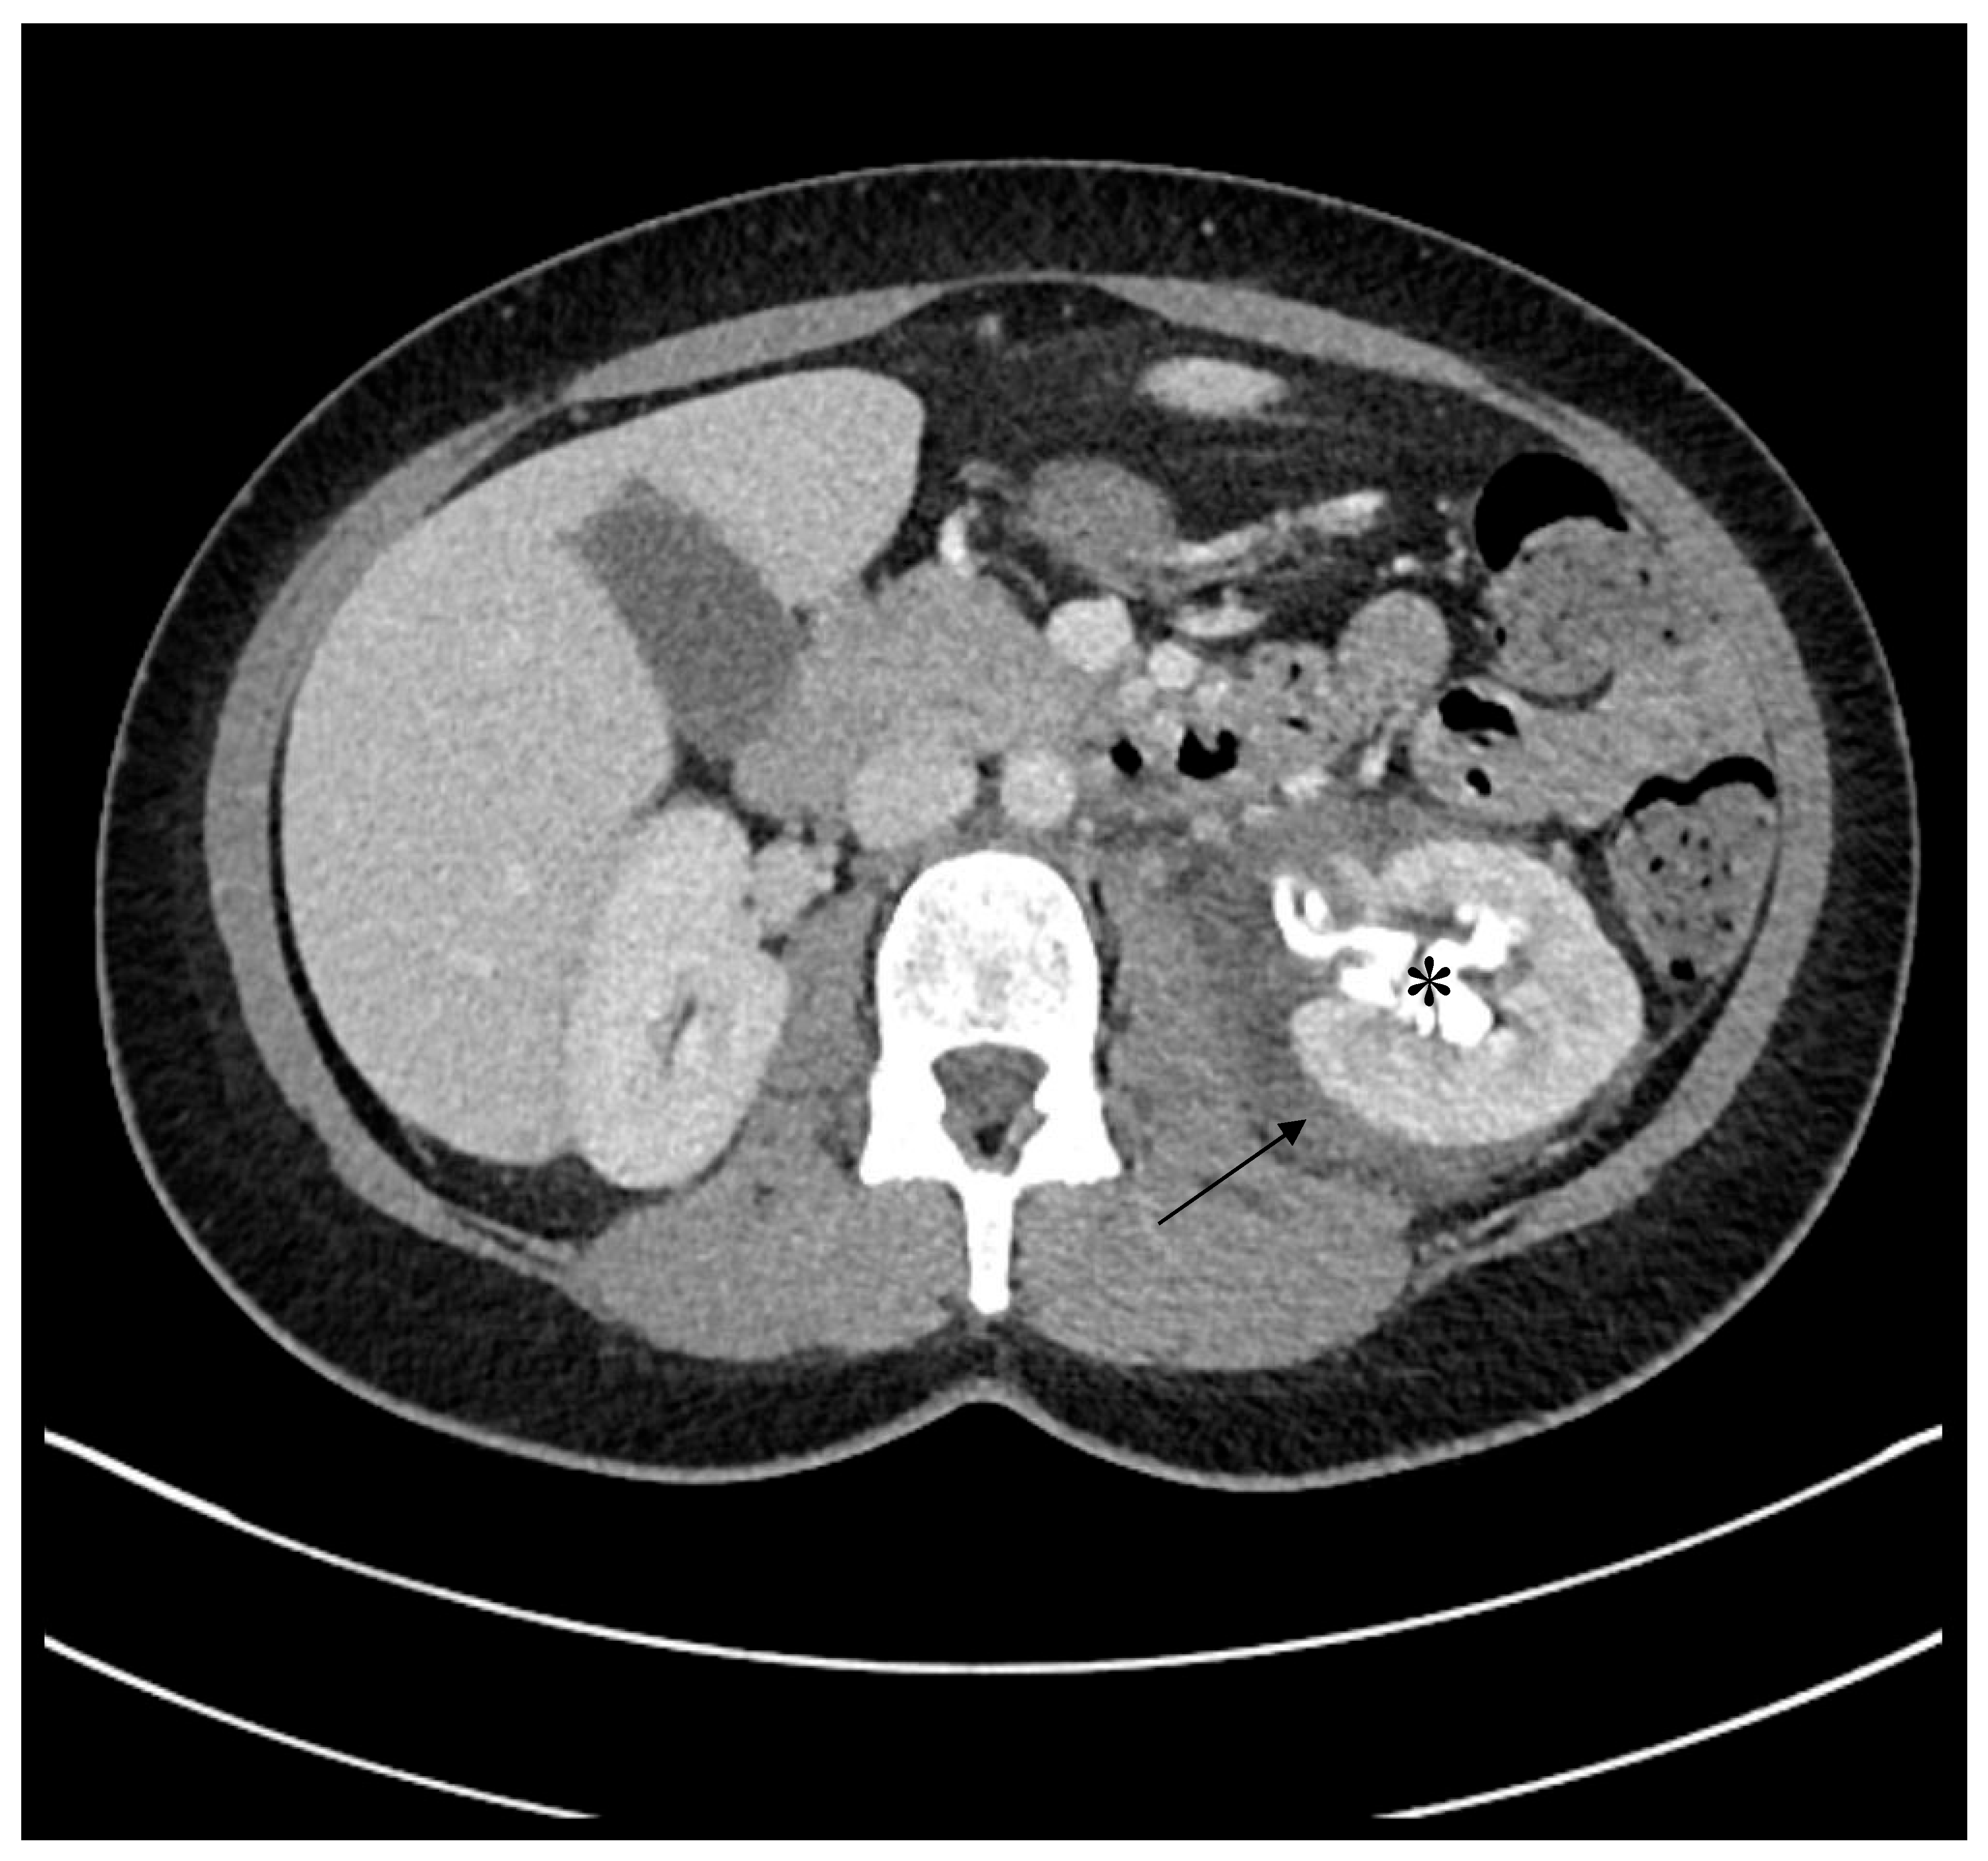

2. Case

4.1. Diagnostic Challenges